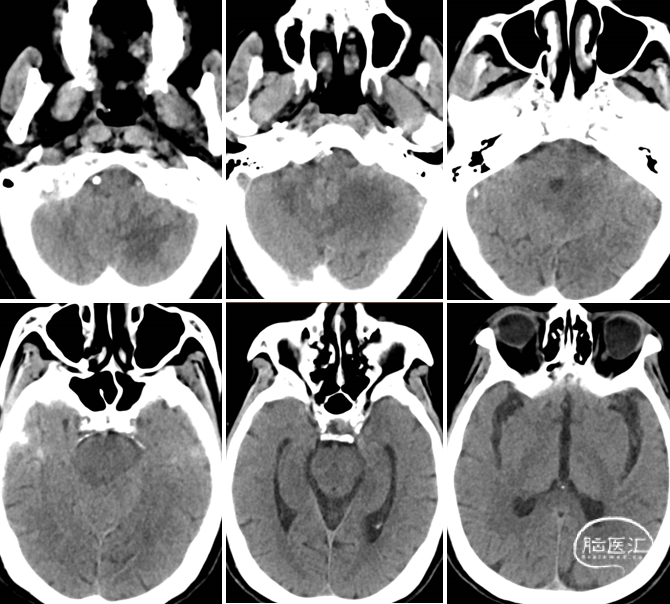

术前CT可见双侧小脑半球及左侧延髓、桥脑梗死灶,桥脑中脑指数2分,pc-ASPECTS评分6分。

CTA示右侧椎动脉V2段及左侧椎动脉V2段远端闭塞可能,左侧后交通动脉开放,基底动脉显影良好。BATMAN评分6分。

术前CT可见双侧小脑半球及右侧桥脑梗死灶,桥脑中脑指数1分,pc-ASPECTS评分6分。

CTA示右侧椎动脉、左侧椎动脉V2段及基底动脉闭塞可能,BATMAN评分1分,右颈内动脉起始段中度狭窄。